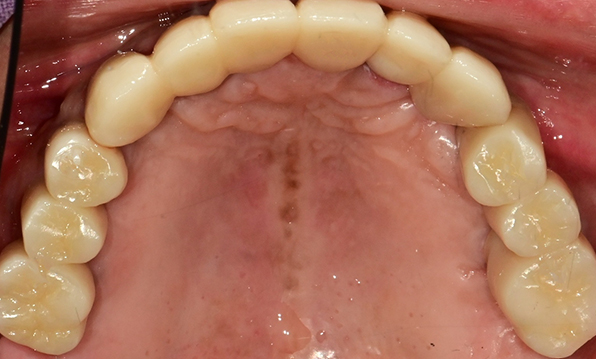

Using a method of placing 8–9 implants in the maxilla and 8 implants in the mandible, this approach fully restores all 28 natural teeth, creating an oral environment most closely resembling

natural dentition.

Before & After

Case 01

Before After